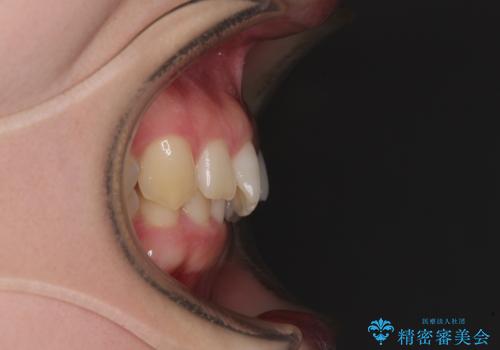

奥歯の咬み合わせを見ると、片方は上顎が下顎に対して相対的に前方にあり、他方は交叉した咬合の状態でした。

咬み合わせを改善するためには、上顎臼歯を後方に移動させた咬み合わせにする必要があります。

インビザライン単体で改善することも可能ですが、ディープバイトのためインビザライン単体で達成する可能性が低いと考えられたため、カリエール・ディスタライザーという補助装置を併用して、より確実性を上げることとしました。

カリエール・ディスタライザーを使用している期間、反対側はワイヤー矯正により叢生を解消していくこととしました。

奥歯の咬み合わせを改善しながら、並行してインビザラインで歯列を整えることとしました。